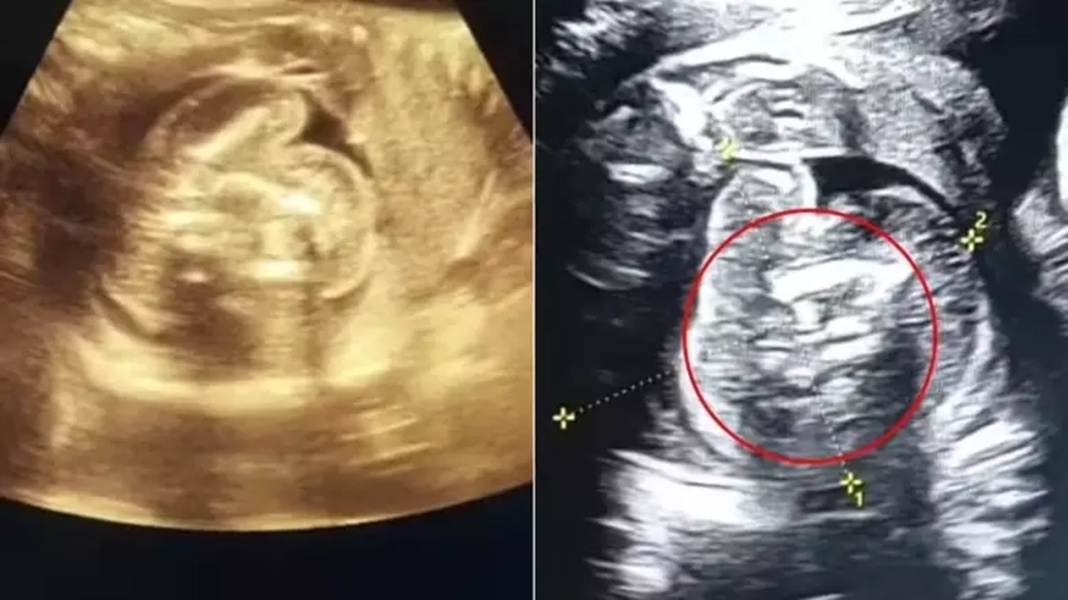

Bebê "engole'' irmãos no útero | Foto: Reprodução/Contigo

Um caso surpreendente ocorreu na Índia e surpreendeu os médicos: uma mulher de 32 anos, grávida de 35 semanas, deu entrada em um hospital para um exame de rotina. Durante a avaliação, os profissionais identificaram que o bebê, um menino, carregava dois fetos em seu abdômen, um fenômeno conhecido como "feto dentro de feto"

Os exames revelaram uma estrutura anormal contendo ossos dentro do bebê, o que levou os médicos a realizarem uma investigação mais aprofundada. À imprensa nacional, o médico responsável pelo caso, Prasad Agarwal, explicou a condição.